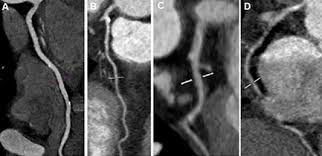

Dual Source technology of this 2008 Definition 128 is the key to accelerating CT imaging. The combination of two sources, a high table feed, ultra-fast data transmission, and a gantry that can perform a full rotation in 0.28 seconds makes the SOMATOM® Definition Flash truly unrivalled when it comes to scanning speed. Its temporal resolution of 75 ms comes with no sacrifices in image quality – instead, it offers remarkable benefits not only for the most dose-sensitive patients: With the Flash Spiral, dose values under 1 mSv are so frequent that they can be considered routine.

Up to 80cm Gantry aperture; OIL/AIR tube cooling; – 60kW output; – Range: 28 to 665mA; – Reconstruction matrices 512×512;